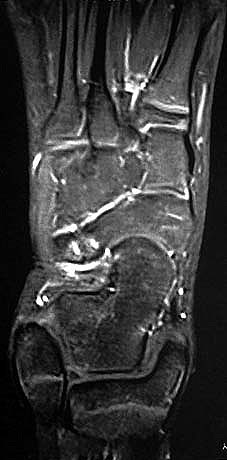

Z.n. Distorsion des Fußes mit „Ruptur“ der (vorbestehenden) talocalcanearen Coalitio. Die Wassereinlagerung in den an die Coalitio angrenzenden knöchernen Bezirken ist im MRT gut zu erkennen. Nach monatelangen Beschwerden spontane Besserung.

Abbildung 1

Die zweite wichtige Form tarsaler Coalitiones findet sich im medialen Bereich des Subtalargelenkes, am häufigsten unter Einbeziehung der medialen, mittleren Facette des talocalcanearen Gelenkes (Abb. 9). Die Ausdehnung der zunächst fibrösen, später zunehmend verknöcherten Brückenbildung kann sehr unterschiedlich Anteile der hinteren Kammer des unteren Sprunggelenkes mitumfassen; auch rein dorsomediale Formen ohne Einbeziehung der medialen Facette werden beobachtet (Abb. 2) 67 (Hamel 2008).

Diagnostisch sollte neben Röntgenübersichtsaufnahmen (indirekte radiologische Zeichen: Dorsaler Traktions-Osteophyt am Taluskopf, „talar beaking“; kontinuierliche Linie der Trochlea-tali-Kontur übergehend in die Sustentaculum-tali-Kontur, „C-Zeichen“ (Abb. 11) 10) immer die dreidimensionale Bildgebung eingesetzt werden. Das MRT (mit Kontrastmittel) kann die Struktur der Brückenbildung und z.B. die Qualität des Restgelenkes (Knorpel-Dicke) besonders gut abbilden; das Dünnschicht-CT zeigt die knöcherne Feinstruktur im Bereich der Coalitio und den oft sehr schrägen Spalt-Verlauf im Frontalschnitt dagegen häufig genauer. Meist findet sich die Überbrückung im Bereich der medialen Facette; die Schichten sollten jedoch bis weit nach dorsal beurteilt werden, da ansonsten dorsomediale Formen übersehen werden können. Rozansky et al 7 unterschieden fünf morphologische Typen auf der Basis von 3-D-CT-Rekonstruktionen. Allerdings ist eine prognostische Zuordnung bisher nicht möglich.